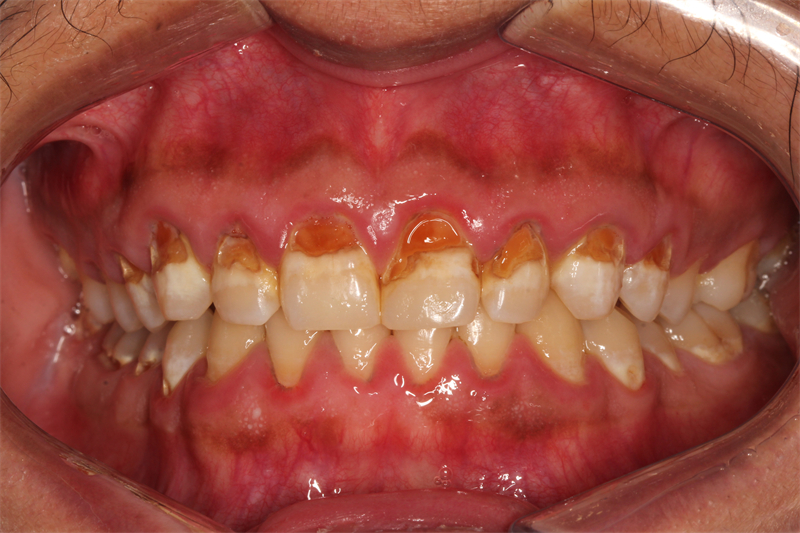

當小程走進柳州市人民醫院口腔科時,心情是忐忑不安的。但在這里,他遇到了認真負責、技術精湛的主診醫師。醫生耐心地詢問了他的病史,并進行了詳細的口腔檢查和X線片檢查。經過一番仔細的檢查后,醫生告訴小程,他患上了一種叫做“可樂牙”的牙齒疾病,臨床上也稱為牙齒酸蝕癥。這是由于長期飲用含糖量高、酸性強的碳酸飲料所導致的牙齒問題。

醫生告訴小程,雖然他的牙齒問題比較嚴重,但還沒有侵蝕到牙髓,因此還是可以通過一系列的治療手段來恢復牙齒的健康和美觀的。經過首席專家團隊的嚴密討論,決定為小程實施全口牙周潔治、涂氟預防以及樹脂充填修復的個性化治療方案。

治療過程中,醫生展現出了極高的專業素養和認真負責的態度。通過細致的牙周潔治、涂氟預防,小程一周后復診自覺嘴巴味道小了很多。然而,由于小程缺損的牙齒太多,為了確保治療效果和患者的舒適度,醫生決定采用分區修復的方法。在橡皮章的嚴密隔濕下,醫生進行了樹脂分層修復。